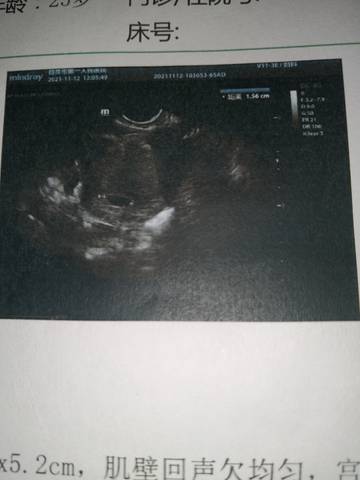

十一月去检查啥都不是今天去检查说十周了有没有会看的?

你好。我们是判断不了男宝宝跟女宝宝的,孕期定期检查,我觉得宝宝健康就好的。祝心想事成 。